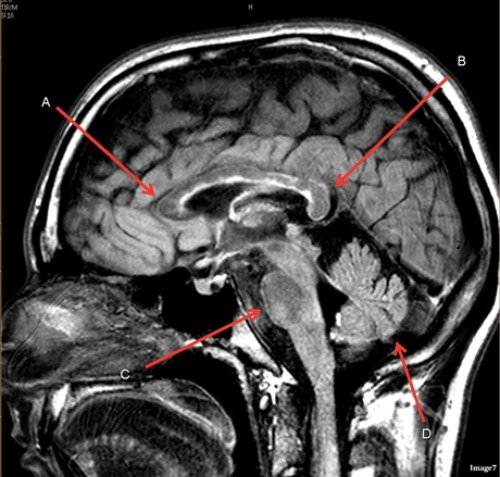

Letter D in Image 7 is pointing to:

A. Pons

B. Cerebellum

C. Hypothalamus

D. Genu of the corpus callosum

E. Splenium of the corpus callosum

Letter A in Image 8 is pointing to:

A. Tentorium

B. Corpus callosum

D. Fourth ventricle

E. Lateral Ventricle

Image 8 is an example of a ____ weighted sequence acquired in the ____ scan plane.

A. T1; Axial

B. T1; Sagittal

C. T2; Axial

D. T2; Sagittal

Letter A in Image 7 is pointing to:

Letter B in Image 7 is pointing to:

Letter C in Image 7 is pointing to:

Image 7 is an example of a _____ weighted sequence acquired in the ______ scan plane.

B. T2 FLAIR; Sagittal

Letter B in Image 8 is pointing to:

E. Medulla oblongata

Letter E in Image 8 is pointing to:

C. Thalamus

Letter F in Image 8 is pointing to: